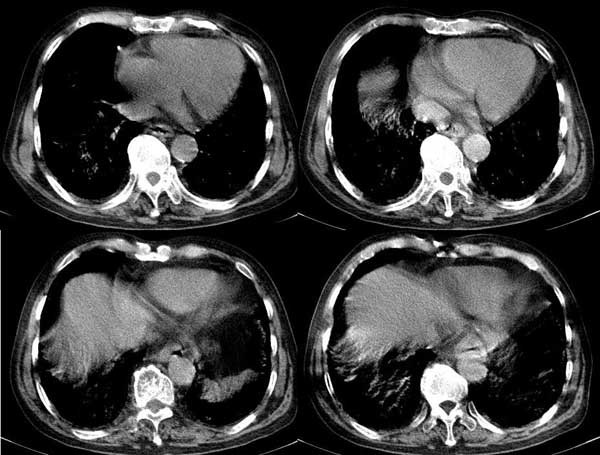

以下是引用dalianren在2006-7-20 21:23:00的发言:[br]我考虑是肺泡蛋白沉积症:典型表现为两肺内散在片状\"磨玻璃\"样混浊区呈地图样分布.

以下是引用lj0804在2006-7-21 12:57:00的发言:[br]支持[br]我考虑是肺泡蛋白沉积症:典型表现为两肺内散在片状\"磨玻璃\"样混浊去呈地图样分布.